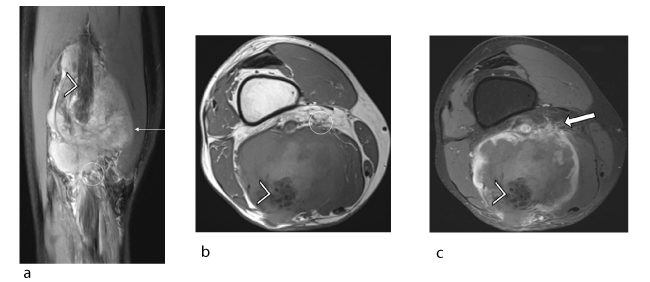

Figure 5. Male patient, 59 years old, suffering from pleural mesothelioma secondary to asbestos exposure. Recent appearance of lump in left thigh: intraneural metastasis of the pleural mesothelioma confirmed histologically. (a) Coronal proton density fat-saturated slice (TR/TE 3000/24) showing the tumour (arrow) with a heterogeneous signal and ill-defined margins (circle) but no target sign. Note the dissection of the hypointense sciatic nerve fascicles (arrowhead) by the hyperintense infiltrating tumour. (b) Axial T1 slice (TR/TE 900/12) showing a large tumour (arrow) centred on the left sciatic nerve (arrowhead) with a heterogeneous signal and ill-defined margins (circle). (c) Axial T1-weighted fat-suppressed post-gadolinium slice showing heterogeneous uptake in the tumour (arrow) with predominantly peripheral uptake and spread into soft tissues (solid arrow). Also note the dissection of the sciatic nerve fascicles (arrowhead).